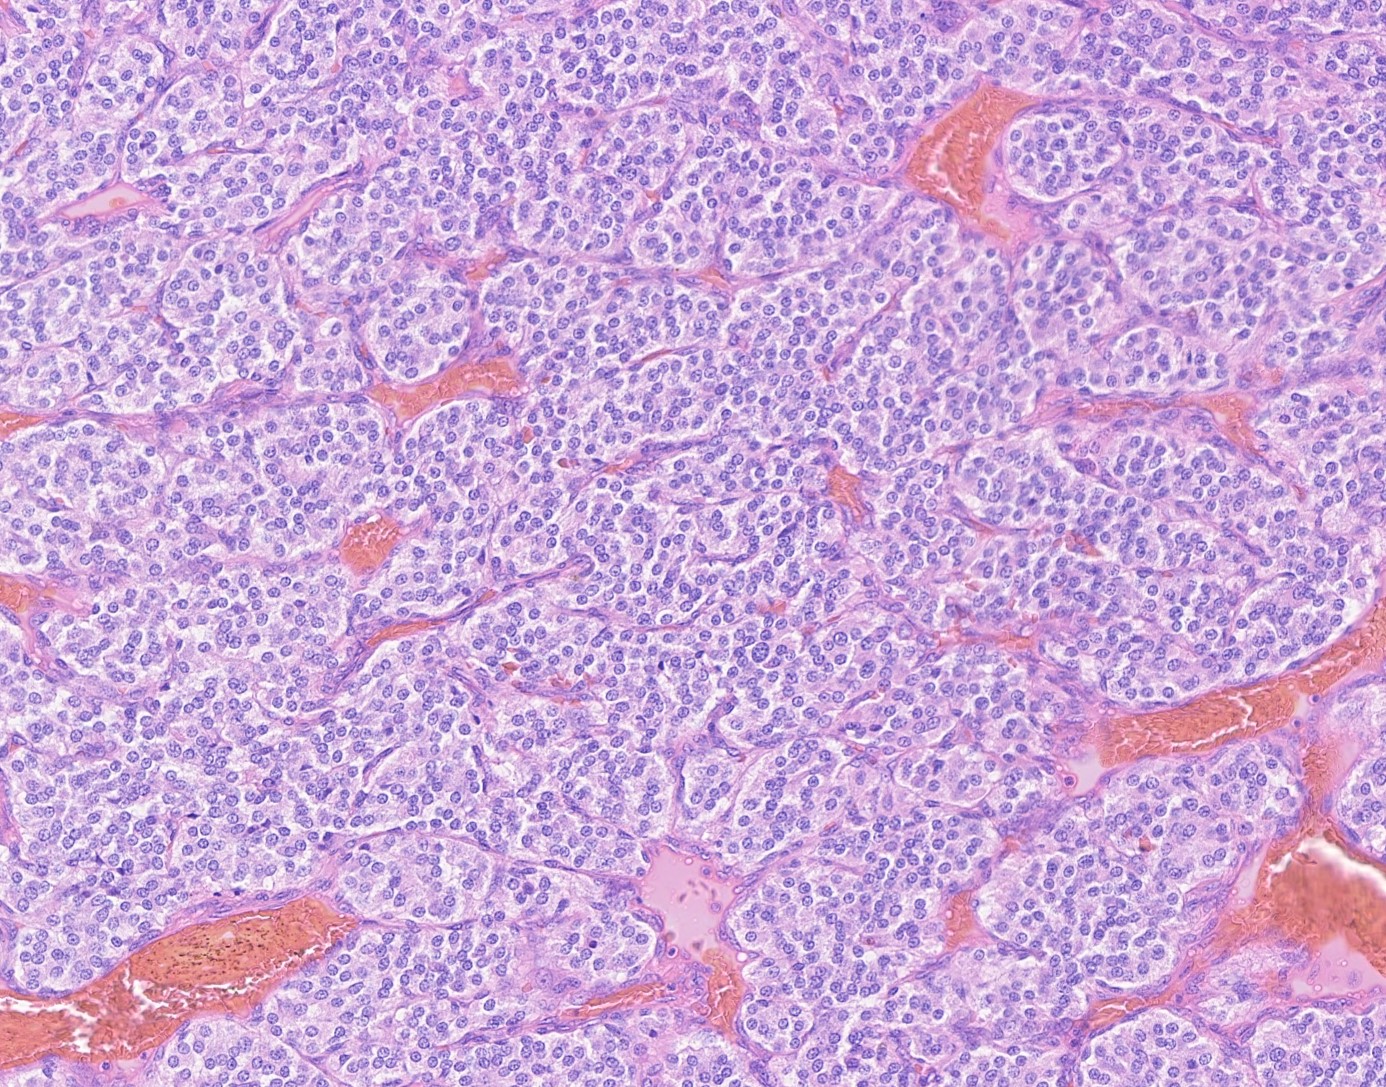

Carotid body paragangliomas are slow growing, well circumscribed tumors with a reddish-brown, firm cut surface. Hemorrhage and cystic degeneration may be seen. On microscopy, nests of oncocytic cells ("zellballen"), often with prominent intranuclear cytoplasmic pseudoinclusions, are surrounded by a fibrovascular network including small spindled sustentacular cells. As demonstrated by this case, an organoid growth pattern is most common in head and neck paragangliomas, but trabecular and solid growth, spindled areas, pigmentation, stromal sclerosis and even amyloid deposition have been described (Head Neck Pathol 2015;9:300). The sustentacular cells stain with S100 and the tumor cells with neuroendocrine markers (synaptophysin, chromogranin, CD56). A reticulin stain will highlight the fibrovascular network. Management is surgical resection (Arch Pathol Lab Med 2014;138:182).

Carotid body paragangliomas are slow growing, well circumscribed tumors with a reddish-brown, firm cut surface. Hemorrhage and cystic degeneration may be seen. On microscopy, nests of oncocytic cells ("zellballen"), often with prominent intranuclear cytoplasmic pseudoinclusions, are surrounded by a fibrovascular network including small spindled sustentacular cells. As demonstrated by this case, an organoid growth pattern is most common in head and neck paragangliomas, but trabecular and solid growth, spindled areas, pigmentation, stromal sclerosis and even amyloid deposition have been described (Head Neck Pathol 2015;9:300). The sustentacular cells stain with S100 and the tumor cells with neuroendocrine markers (synaptophysin, chromogranin, CD56). A reticulin stain will highlight the fibrovascular network. Management is surgical resection (Arch Pathol Lab Med 2014;138:182).